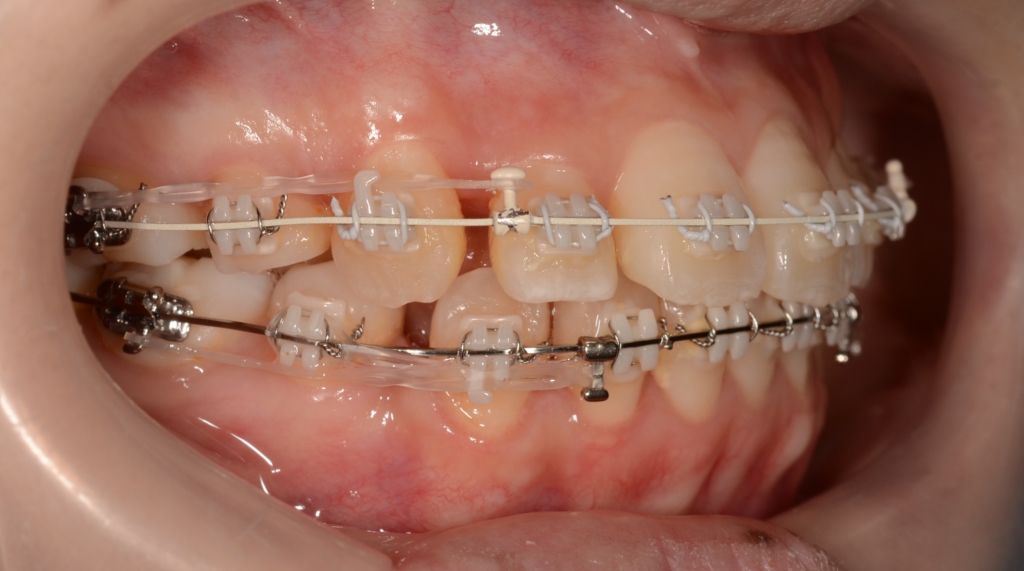

【Before】

マルチブラケットシステム(ハーフホワイトtype)で矯正を開始。

ハーフホワイトtypeのマルチブラケットシステム